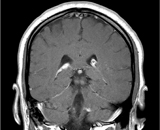

Neurosarcoidosis (sometimes shortened to neurosarcoid) refers tosarcoidosis, a condition of unknown cause featuring granulomas in various tissues, involving the central nervous system (brain and spinal cord). It can have many manifestations, but abnormalities of the cranial nerves (a group of twelve nerves supplying the head and neck area) are the most common. It may develop acutely, subacutely, and chronically. Approximately 5-10% of people with sarcoidosis of other organs (e.g. lung) develop central nervous system involvement. Only 1% of people with sarcoidosis will have neurosarcoidosis alone without involvement of any other organs.